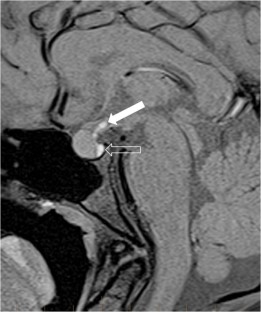

We selected pediatric head MRI examinations from 2005 to 2017 based on the finding of a double midline sellar and suprasellar bright spot on T1-weighted sequence. Medical history, physical examination, pituitary hormonal profile and bone age evaluation were extracted from the medical record of the selected patients. An experienced pediatric neuroradiologist reviewed head MRIs, which were performed on 3-tesla (T) magnet and included at least sagittal T1-weighted imaging centered on the sella turcica obtained with and without fat suppression.

In six cases, two midline bright spots were identified on T1-weighted sequences obtained both with and without fat suppression. While one spot was located at the expected site of the neurohypophysis in the posterior sella, the second one was in the region of the median eminence, suggesting partial ectopic posterior pituitary gland. Growth hormone deficiency, either isolated (n=1) or combined with thyroid stimulating hormone deficiency (n=1) was found. None of the children had clinical signs of posterior pituitary dysfunction.

Fig. 2